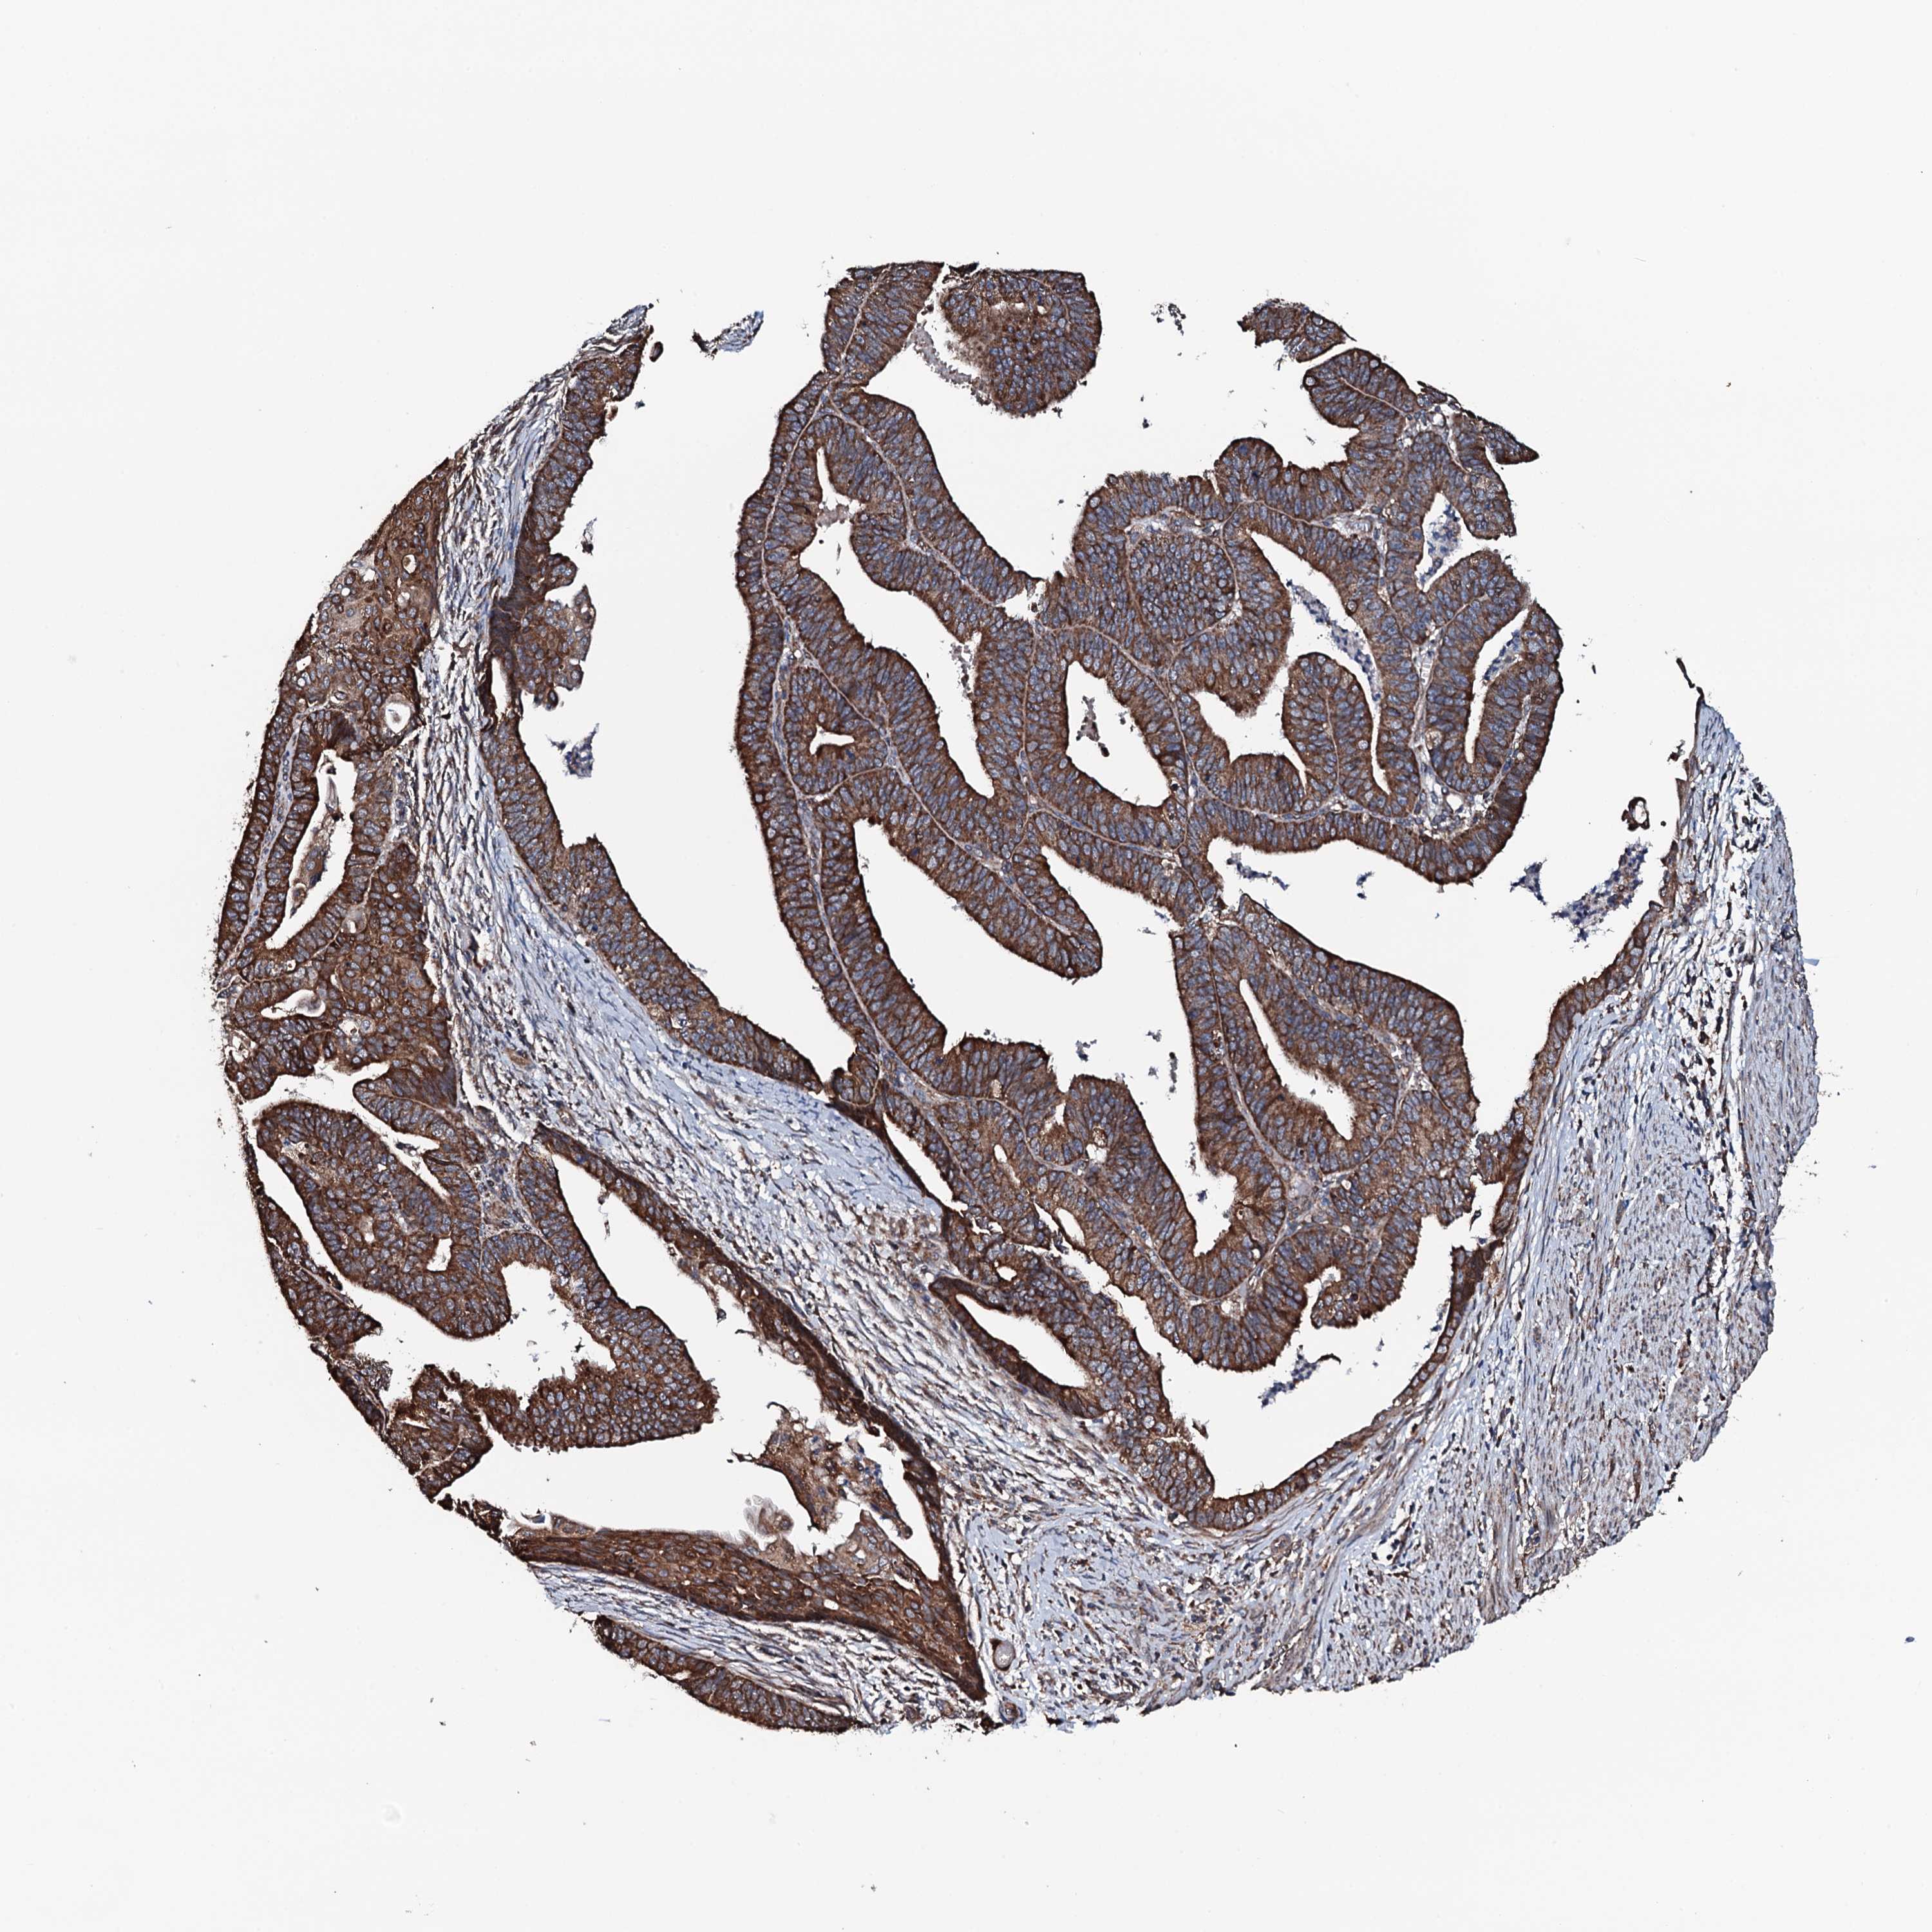

ENDOMETRIAL CANCER - Protein expressioni

A mouse-over function shows sample information and annotation data. Click on an image to view it in a full screen mode. Samples can be filtered based on level of antibody staining by selecting one or several of the following categories: high, medium, low and not detected. The assay and annotation is described here.

Note that samples used for immunohistochemistry by the Human Protein Atlas do not correspond to samples in the TCGA dataset.

Antibody stainingi

Antibody staining in the annotated cell types in the current human tissue is reported as not detected, low, medium, or high, based on conventional immunohistochemistry profiling in selected tissues. This score is based on the combination of the staining intensity and fraction of stained cells.

Each image is clickable and will lead to virtual microscopy that enables deeper exploration of all samples and also displays staining intensity scores, fraction scores and subcellular localization as well as patient and tissue information for each sample.

Antibody HPA040727

Staining

High

Medium

Low

Not detected

Intensity

Strong

Moderate

Weak

Negative

Quantity

>75%

75%-25%

<25%

None

Location

Nuclear

Cytoplasmic/membranous

Cytoplasmic/membranous,nuclear

Adenocarcinoma, NOS